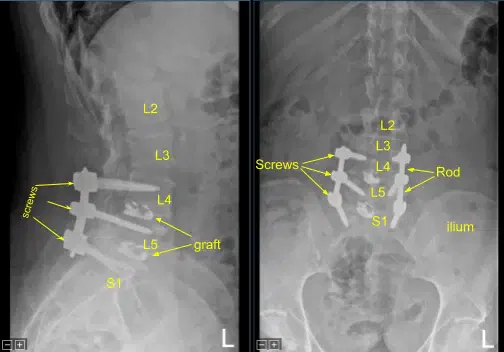

Se obtuvo una tomografía computarizada intraoperatoria, los datos se transfirieron al ordenador de neuronavegación y se verificó la precisión. Se utilizaron técnicas de neuronavegación para canular el primer segmento sacro derecho que luego se palpaba en busca de rupturas y se medía a una profundidad de 35 mm. Se utilizaba un tapón de 6,0 mm para enhebrar la canulación. De nuevo se palpó para detectar brechas y se colocó un tornillo pedicular de titanio de 7,5 x 35 mm con buen sujeito óseo y firmeza.

A continuación, se volvió a colocar el drapado al paciente y se realizó una segunda tomografía computarizada intraoperatoria que mostró la correcta posición de este tornillo pedicular. Las señales de neuromonitorización se mantuvieron estables en todo momento. A continuación, el proceso transversal L5-S1 y ala fueron decorificados con un taladro de alta velocidad para la artrodesis tras explorar la fusión y no identificar la artrodesis ósea ni el injerto óseo.

De nuevo, se colocó una varilla de titanio precortada precortada sobre los tulipanes de tornillo pedículo desde L4 hasta S1 y se aseguró con las tapas de bloqueo, que se apretaron con un dispositivo de par y antitorque. Se colocó un aloinjerto óseo morcelizado en L5-S1 en el lado derecho para la artrodesis.

La pequeña dehiscencia en la incisión del lado izquierdo fue desbridada y la piel se volvió a cerrar. Todas las incisiones se limpiaron y secaron de forma estéril, y los apósitos se aplicaron de forma estéril. Se aplicó un recipiente Hemovac con succión. La unidad C-arm se cubría de forma estéril y se utilizaba para la confirmación por AP y fluoroscopia lateral del correcto hardware y la posición de la instrumentación, específicamente la colocación de las varillas.